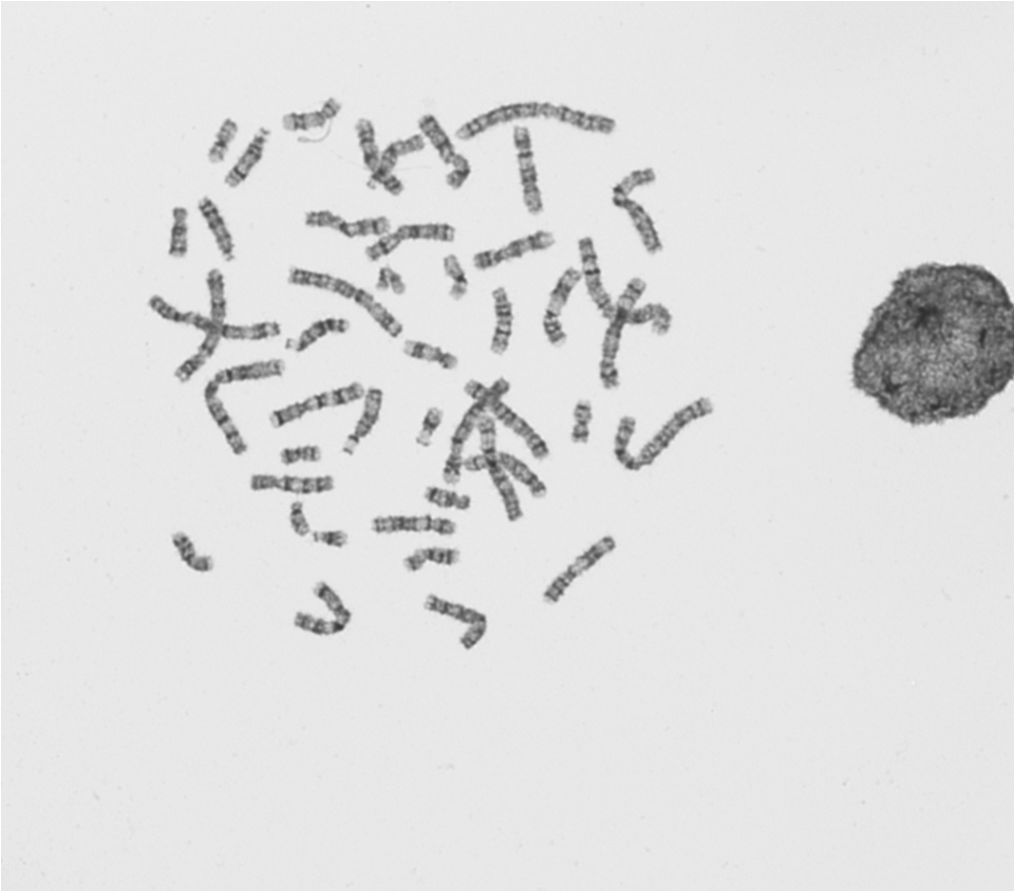

Images des métaphases non améliorées : GTG

- EEQ_SG_2019-GTG-01.JPG (49.95 Kio) Vu 55207 fois